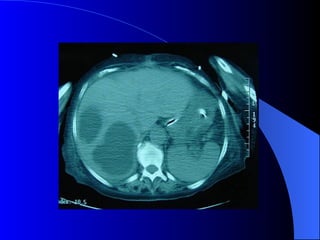

Absceso hepático piógeno DX por imágenes. Ecografia y TAC. Clínica Generalmente secundario.

Absceso Hepático